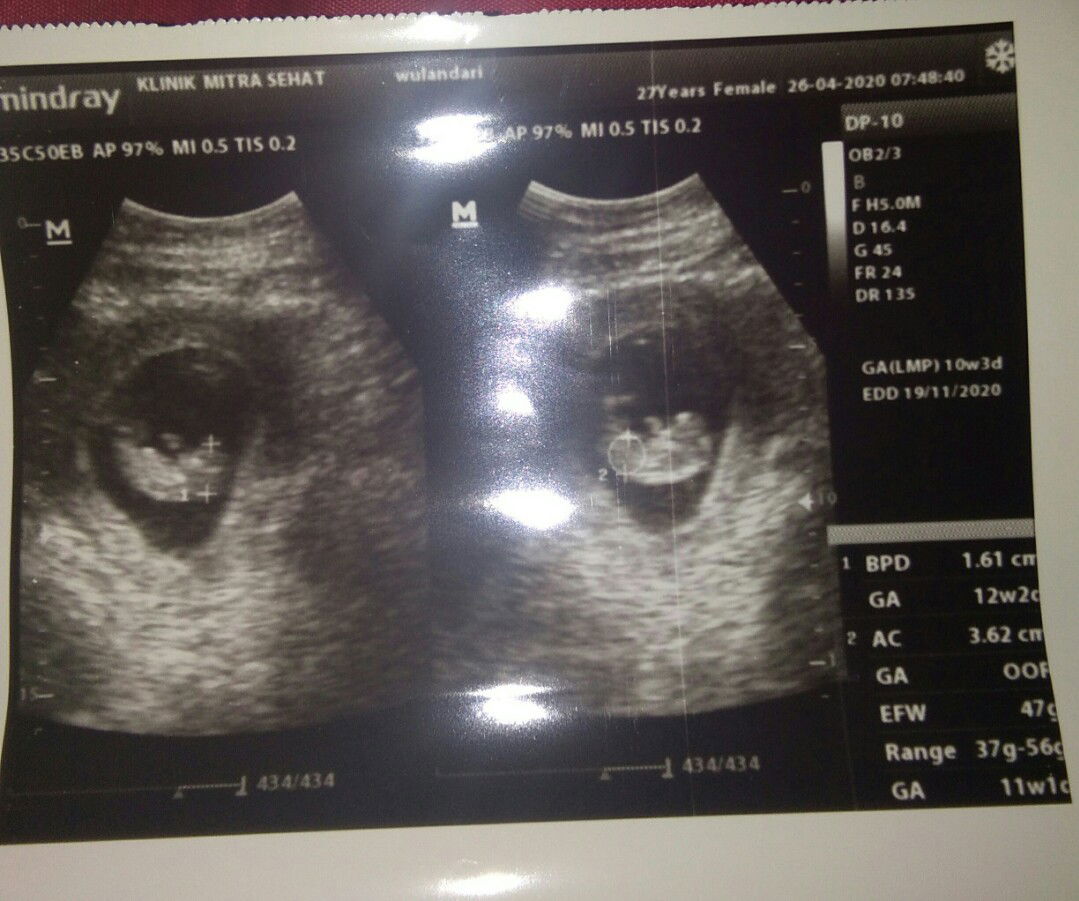

Di usg bukn 10wbun tpi 12w2d... Smoga sehat terus ya bun